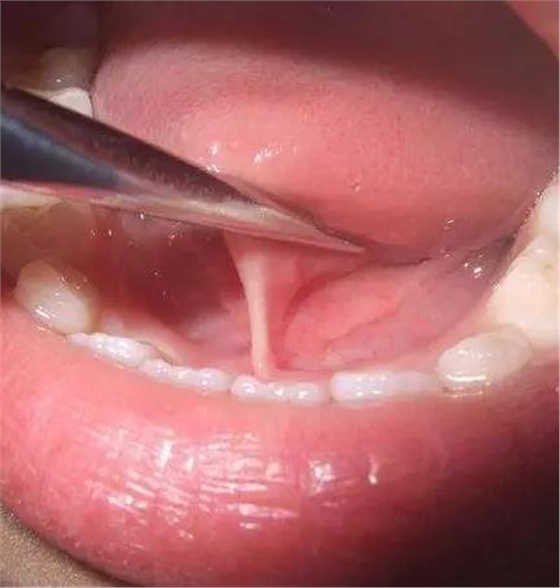

舌筋,是舌系帶的俗稱。舌系帶即孩子張開(kāi)口翹起舌頭時(shí)在舌和口底之間的一薄條狀組織,它是舌下區(qū)黏膜在中線形成的連接舌下與齒槽的一條黏膜系帶。正常情況下新生兒的舌系帶是延伸到舌尖或接近舌尖的。在舌的發(fā)育過(guò)程中,系帶會(huì)逐漸向舌根部退縮,所以嬰幼兒并非一出生就能舌頭伸轉(zhuǎn)自如,而是從短小到剛能夠吸吮開(kāi)始,之后由于喝奶、言語(yǔ)需求所迫開(kāi)始發(fā)音等,經(jīng)過(guò)長(zhǎng)達(dá)數(shù)年的一系列相關(guān)的漫長(zhǎng)活動(dòng)與練習(xí),這才使得孩子的舌尖逐漸遠(yuǎn)離系帶,從而走向正常。

舌系帶短,是一種先天性發(fā)育異常,主要表現(xiàn)為舌底下正中處的舌系帶過(guò)短,使舌的正常活動(dòng)受到限制,舌頭因而不能伸長(zhǎng)到口外,或往上不能接觸上唇;舌前伸時(shí),因舌系帶短拉著舌頭,使舌頭的背面有小的凹陷,舌尖部則呈"V"型或"W"型。嚴(yán)重者影響吸吮,影響語(yǔ)音清晰度和學(xué)語(yǔ)。人們俗稱為“大舌頭”就是這種情況造成的。

如果舌系帶一頭附著在舌尖,另一頭附著口腔底的前側(cè),這樣就限制住舌頭的運(yùn)動(dòng),向外不能伸出口外,向上又舔不到上腭,這時(shí)才可以判斷為舌系帶過(guò)短。一般來(lái)說(shuō),最好觀察到2歲以后,這時(shí)候舌尖開(kāi)始逐漸遠(yuǎn)離系帶,如果確因系帶過(guò)短影響舌前伸,甚至妨礙語(yǔ)言清晰,可以進(jìn)行診斷并尋求進(jìn)一步的治療。